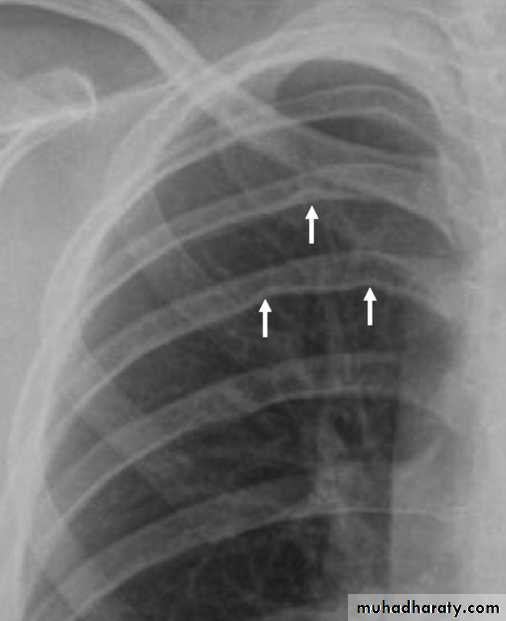

Linear(discoid)atelectasis : is not secondary to bronchial obst., but due to hypoventilation, commonest cause is postop. Or post traumatic pain. The result is horizontally oriented band or disc of collapse

RUL collapse +Golden S sign